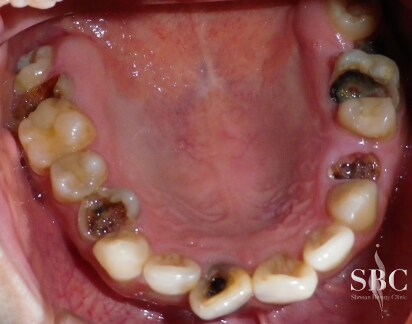

No.59677【インプラント・歯科その他】歯が全体的にボロボロでも大丈夫!Dr金子執刀★失った歯を取り戻す!OSSTEMインプラント

全体的に虫歯だらけ(:_;)抜歯とインプラント★噛む面からのお写真

抜歯とインプラント後のお写真